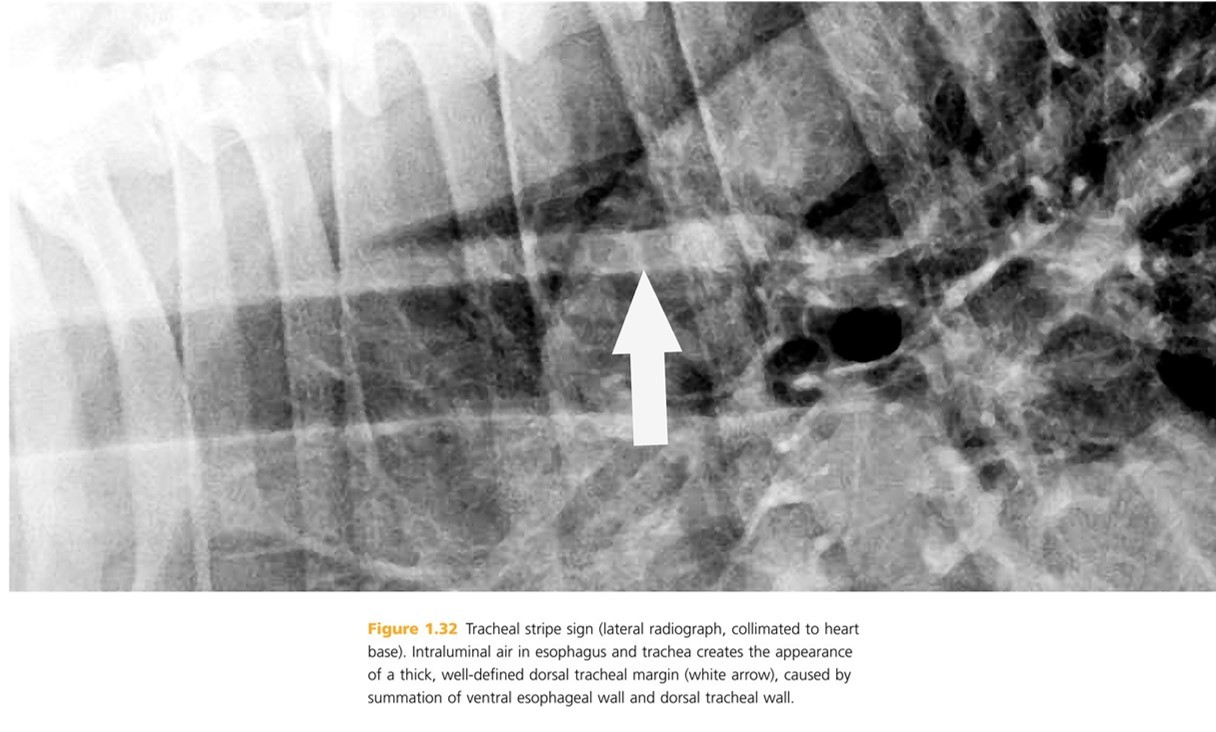

tracheoesophageal stripe sign (a.k.a tracheal stripe)

Occurs when the esophagus contains gas and the ventral esophageal wall blends with the dorsal tracheal wall to mimic false thickening of the tracheal wall (sign indicates presence of gas in the esophagus). Other name; tracheal stripe sign.